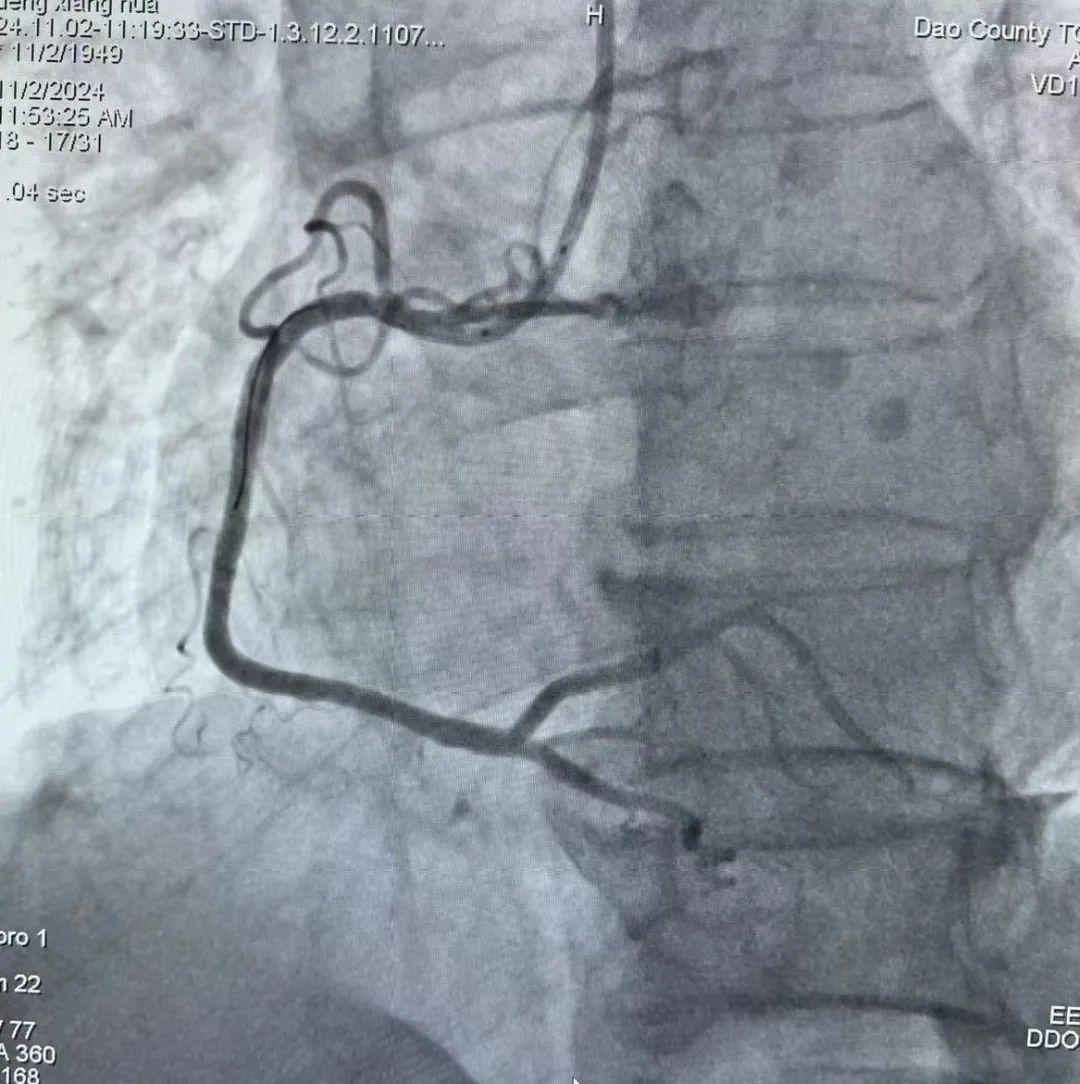

患者李某,男性,76岁因胸闷2小时呼叫120,院前完善心电图后考虑急性心肌梗塞,予以一键启动,给药、预谈话,畅通绿色通道,绕行急诊、绕行病房,急诊冠脉造影示右冠近段以下完全闭塞,急诊PCI,D t W 24分钟,胸痛症状缓解,转入病房后生命体征平稳。